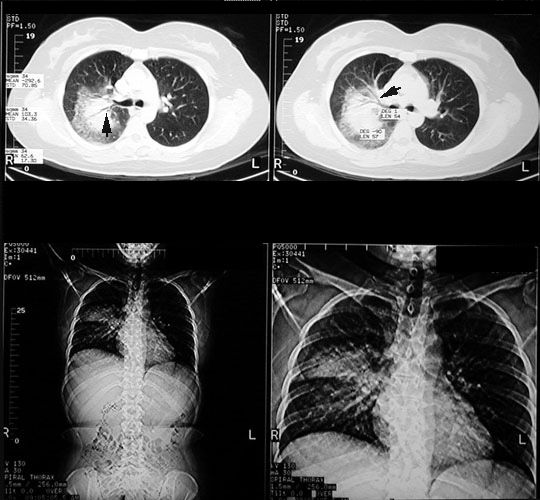

CT scan showing RUL round density with air bronchogram (arrows) suggesting air space disease.